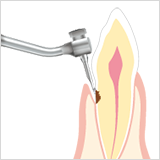

• Diamant beschichtete kugelförmige Spitze. Blutungen treten seltener auf.

• Diamant-Beschichtung

• Für NSK

• Diamant beschichtete kugelförmige Spitze. Blutungen treten seltener auf.

• Diamant-Beschichtung

• Bei molarer und interdentaler proximaler Karies. Mit der halbkugelförmigen Spitze wird das Schneiden in den gesunden Zahn vermieden.

• Diamant-Beschichtung

• Für anteriore proximale Karies. Nur kariöses Dentin kann entfernt werden, z. B. bei Molaren.

• Bei molarer und interdentaler proximaler Karies. Mit der halbkugelförmigen Spitze wird das Schneiden in den gesunden Zahn vermieden.

• Für anteriore proximale Karies. Nur kariöses Dentin kann entfernt werden, z. B. bei Molaren.